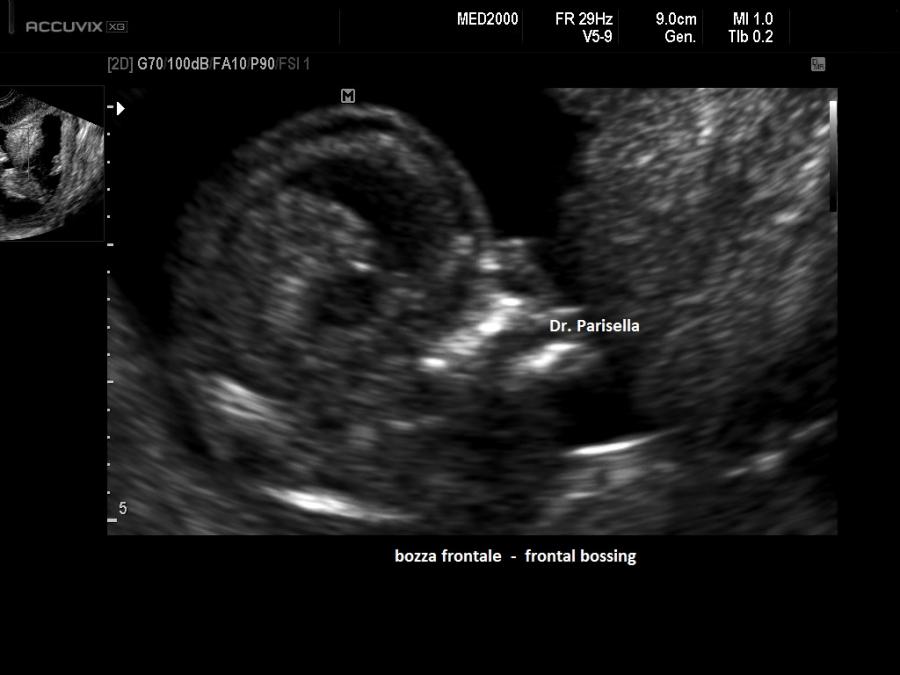

Dal punto di vista ecografico il tratto rizomelico è estremamente ipoplasico, ricurvo e con le metafisi slargate (Femore a Cornetta di Telefono) -  (il riconoscimento del Femore a Cornetta di Telefono rappresenta un segno importantissimo e sufficiente per porre con certezza la diagnosi di Displasia Tanatofora tipo I); vi sono coste corte con ipoplasia toracica e si osserva il classico gradino al passaggio tra torace ipoplasico e addome apparentemente prevalente; vi è in genere macrocrania con bozze frontali prominenti (frontal bossing) e naso a sella. Si associa polidramnios severo.